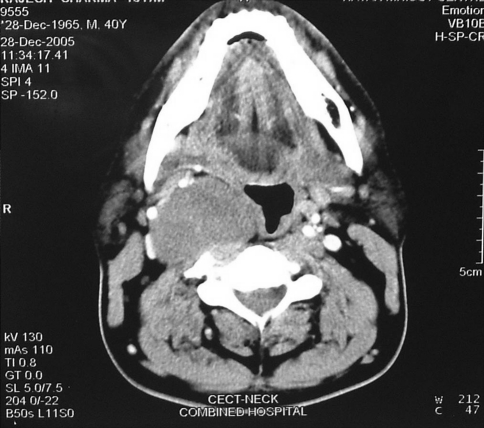

40 year old male presented with complaints of odynophagia for 2 months. There was no history of any lump neck, hoarseness, nasal regurgitation, sore throat, otalgia or weight loss. Examination revealed a visible bulge of the right tonsil and right posterior pillar (Fig. 1). Neck examination showed a diffuse bulge below angle of right mandible. There were no palpable neck nodes. Indirect laryngoscopy showed a bulge of right lateral pharyngeal wall with epiglottis being pushed slightly to the left. However both vocal cords were mobile. Cranial nerve examination was normal. A provisional diagnosis of Right parapharyngeal mass was made. Contrast enhanced CT scan of the neck showed a 6 cm × 5 cm × 3.6 cm size circumscribed mass occupying right parapharyngeal space with peripheral rim enhancement (Fig. 2). There was no involvement of neck vessels and there were no neck nodes. FNAC of the mass was suggestive of a schwannoma. Patient was taken up for excision of the mass through a transcervical approach. Common facial vein and facial artery were ligated and submandibular gland retracted up. Right sternocleidomastoid was retracted and carotid sheath was opened. The tumor was found to be arising from the cervical sympathetic chain just above and posterior to the bifurcation of carotid artery (Fig. 3). The internal jugular vein was found displaced laterally and right vagus was found to be intact. The tumor was found to be well encapsulated and by blunt dissection the superior and inferior aspect of the tumor was identified and the tumor was excised (Fig. 4) along with an intervening segment of the nerve. Post operatively he was found to have developed Horners’ syndrome however patient himself was asymptomatic. Grossly the excised tumor measured 6 cm × 5 cm × 4.5 cm. Microscopic sections of the tumor areas revealed sheets of spindle shaped cells (nerve cells) (Fig. 5) which were at places forming palisaded nuclei (Verocay bodies). Both cellular (Antoni A) and hypocellular, loose and degenerative (Antoni B) areas were seen. Impression was of a schwannoma.

Fig. 2.

CECT neck showing the parapharyngeal mass occuping the poststyloid compartment